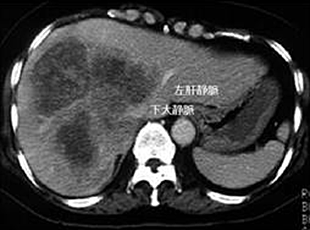

2. Ante-situm法による肝切除

肝静脈根部に腫瘍が存在して通常の肝切除では切除不可能な症例に対して生体肝移植の技術を応用した体内冷却肝灌流法を用いたAnte-situm法による肝切除を行っています。下大静脈が腫瘍の浸潤を受けている場合には人工血管による置換を行います。これまでの実績は8例(京都大学で5例、秋田大学で3例)です。この手術の概要は2005年8月10日に秋田さきがけ新報の「医療新世紀・進むがん治療・秋田大学医学部の取り組み」に紹介されました。(手技は確立されておりますが、試験的手術法の段階であり、一般的治療法では助けられない患者さんに限って考慮しております。)